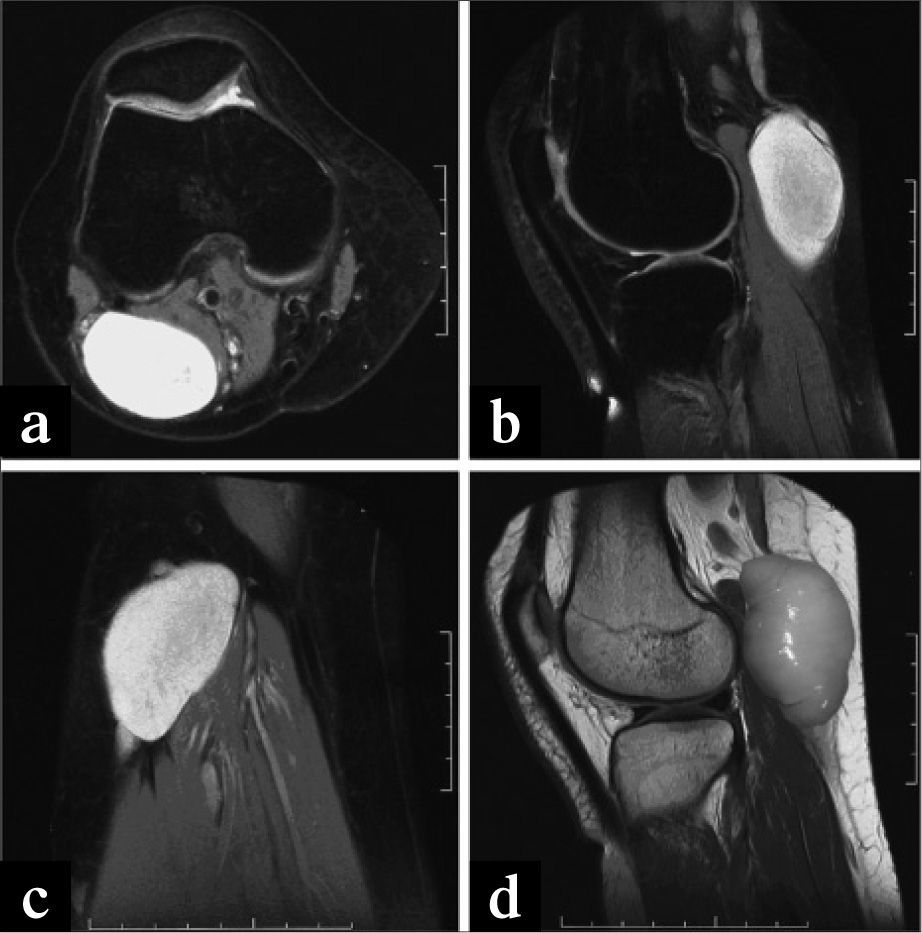

En la exploración se aprecia tumoración sólida (Fig. 1a), rodadera, de gran tamaño, sin adherencia a planos profundos, ocupando completamente la fosa poplítea. Pulsos arteriales normales a todos los niveles.

La exploración con eco-Doppler revela permeabilidad de vena safena externa y de arteria y vena poplíteas, pero muy desplazadas de su eje, y una tumoración sólida en íntimo contacto con la vena poplítea que no cumplía criterios de quiste de Baker y en la que no existía una conexión clara con la cavidad articular, por lo que se decidió realizar una angio-RM.

En la angio-RM se detecta una formación de localización posteroexterna en hueco poplíteo, de paredes lisas, sin conexión con la cápsula articular, desplazando el eje vascular y de dimensiones de 60mm × 40mm (Fig. 2). En la anamnesis y exploración completa no aparecía indicio de neurofibromas en otras partes del cuerpo.

Bajo anestesia general y en posición de decúbito prono (Fig. 1b) se realizó un abordaje posterior e incisión en "S itálica" en hueco poplíteo. Al abrir la fascia, la tumoración sólida se hernió espontáneamente (Fig. 3a). No tenía conexión con el paquete vascular, pero dependía íntimamente del trayecto nervioso ciático poplíteo externo. Finalmente se extirpó en su totalidad.